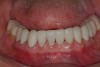

Figure 30  Final restorations.

Figure 30

Figure 31  Technical precision and artistic skill blend into pleasing smile and happy patient.

Figure 31